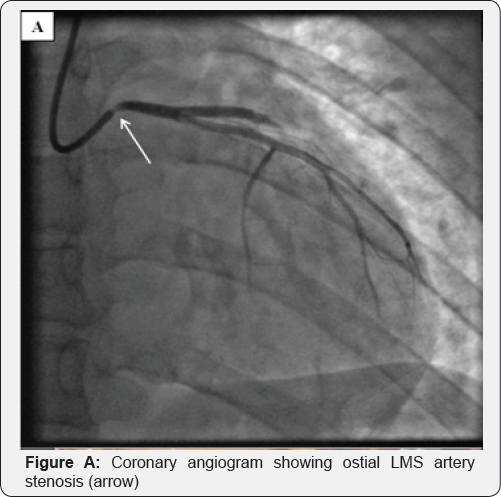

A 27-year-old Caucasian lady was admitted with chest pain at rest suggestive of myocardial ischemia. Clinical examination was normal. The electrocardiogram showed lateral T-wave inversion. High-sensitivity troponin T level was elevated at 18ng/L (99thcentile 13ng/L). The CRP was 32mg/L and normalised within 24 hours. Echocardiography showed anterior wall hypokinesia with good left ventricular function and a normal AV. She was treated with aspirin, clopidogrel and enoxaparin. Coronary angiography showed severe ostial left main stem (LMS) artery stenosis (Figure A) but otherwise normal coronary arteries. Magnetic resonance imaging (MRI) showed a structurally normal aorta and branch aortic vessels, with no evidence of inflammation. She had a background of a seronegative inflammatory polyarthritis with uveitis, both of which were quiescent. An autoantibody screen, C3/C4 complements levels, syphilis and virology screen were normal.

Coronary artery intravascular ultrasound (IVUS) confirmed ostial luminal narrowing of the LMS artery due to adventitial constriction rather than atheroma. A drug-eluting stent (DES) was implanted. The initial diagnosis was that of a localised aortitis but steroids were not initiated given her lack of systemic symptoms, normal inflammatory markers and absence of vasculitis elsewhere.